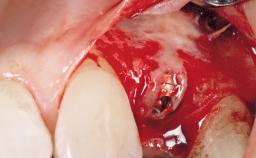

Implant Placement with Simultaneous Contour Augmentation using GBR

Surgical treatment of a 67-year-old male patient exhibiting an extended edentulous space in the anterior maxilla after the removal of three hopeless incisor teeth.

The video demonstrates implant placement using a surgical stent according to the principle of prosthodontically driven implant placement. The deficient ridge is augmented with locally harvested autologous bone chips, a superficial layer of xenogenic DBBM particles and a resorbable collagen membrane. The surgery is completed with a precise, tension-free primary wound closure.

The case concludes with the presentation of the final prosthesis and the esthetic outcome, demonstrating stable soft tissue conditions and stable bone crest levels at the 3-year follow-up.